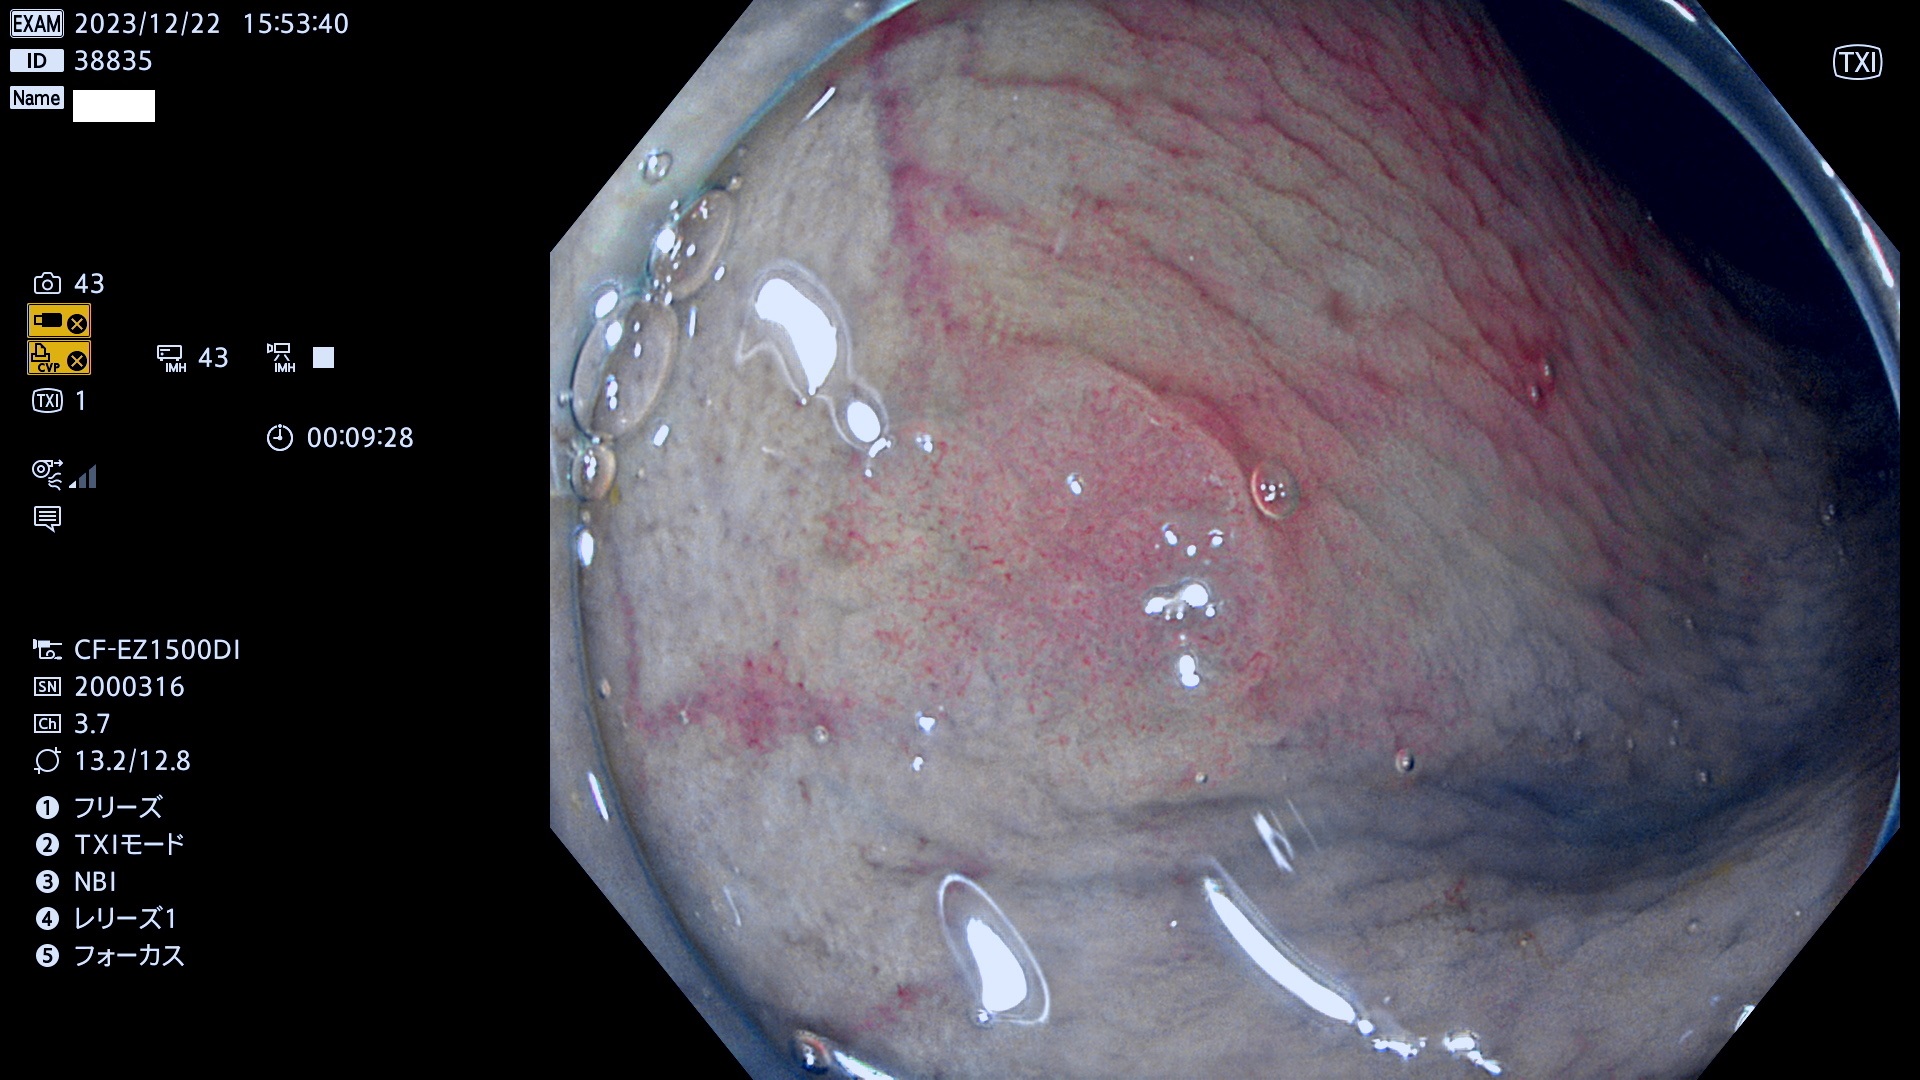

表面型腺腫(Flat Adenoma)の中で、完全に平坦な物をUb、陥凹している物をUcと呼びます。平坦隆起型(Ua)よりも、発見が難しく危険な病変です。

抽出の対象期間 2023年12月21日(木)〜12月24(日)の4日間(48件の検査)6件

当院で見つかった、炎症(ビラン)と極めて紛らわしい腺腫の例